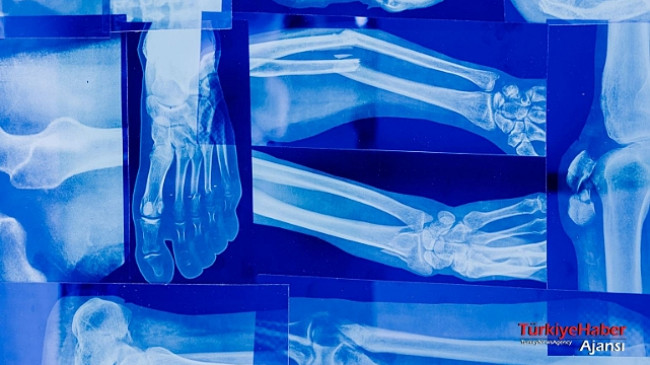

Yüzyılın felaketini yaşadığımız bugünlerde ülke olarak hepimiz büyük acılar içindeyiz. Deprem esnasında düşmeye bağlı ya da enkaz altından çıkarılan depremzedelerin büyük çoğunluğunda kemik kırıkları oluştu.

Kemik kırığındaki belirtilere bakacak olursak, kırığın yerine ve şekline bağlı olarak farklılıklar gösterse de, genel olarak hareketle ve hareketsizken oluşan şiddetli ağrı, bölgesel şişlik, ödem, kanama, ısı artışı ve şekil bozukluğu gibi belirtilerdir. Kırığın tam teşhisinin konulabilmesi için röntgen ve bilgisayarlı tomografi gibi görüntüleme yöntemlerinden faydalanılabilir. Genellikle kırıklar, röntgen görüntüleriyle tespit edilebilirken, daha küçük kemiklerde bulunan bazı kırıklar sadece bilgisayarlı tomografide görüntülenebilmektedir.